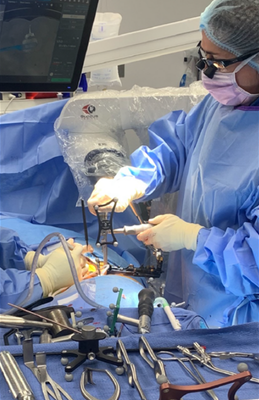

Led by UCSF fellowship-trained Dr. Carrer, we provide board-certified expertise for complex spine conditions and acute injuries.

At the Comprehensive Orthopaedic & Spine Institute, our objective is simple: to provide a practice where patients can access the full gamut of musculoskeletal treatments under one roof. Whether you are suffering from acute sports injuries, overuse conditions, occupational injuries, or high-energy trauma from motor vehicle accidents, we are here to guide you back to health.

- Extensive Surgical Experience with both minimally invasive and complex reconstructive procedures

Dr. Carrer leads a multidisciplinary team that provides access to the full gamut of musculoskeletal treatments, from acute sports injuries and occupational trauma to complex spine surgery. Our unique holistic approach integrates traditional medicine with alternative therapies, connecting you with a network of physiatrists, pain management specialists, chiropractors, and nutritionists all working in unison to optimize your health. Whether you are recovering from a motor vehicle accident or seeking relief from chronic overuse conditions, our goal is to empower you through education, innovation, and compassionate, personalized care.